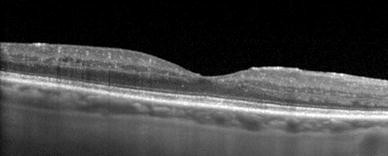

Enhanced depth imaging (EDI) scanning protocols allow non-invasive visualization of the choroid using optical coherence tomography (OCT) (Spectralis, Heidelberg Engineering)